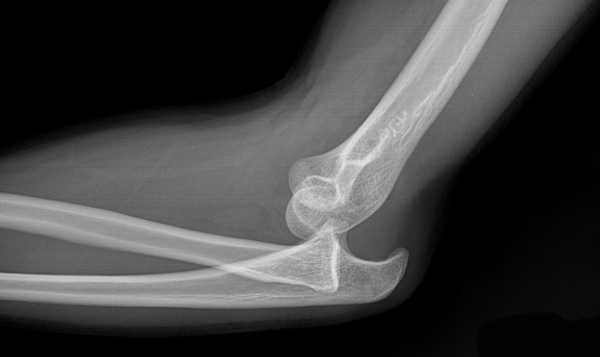

شکستگی ها

Fractures

دررفتگی ها

Dislocations